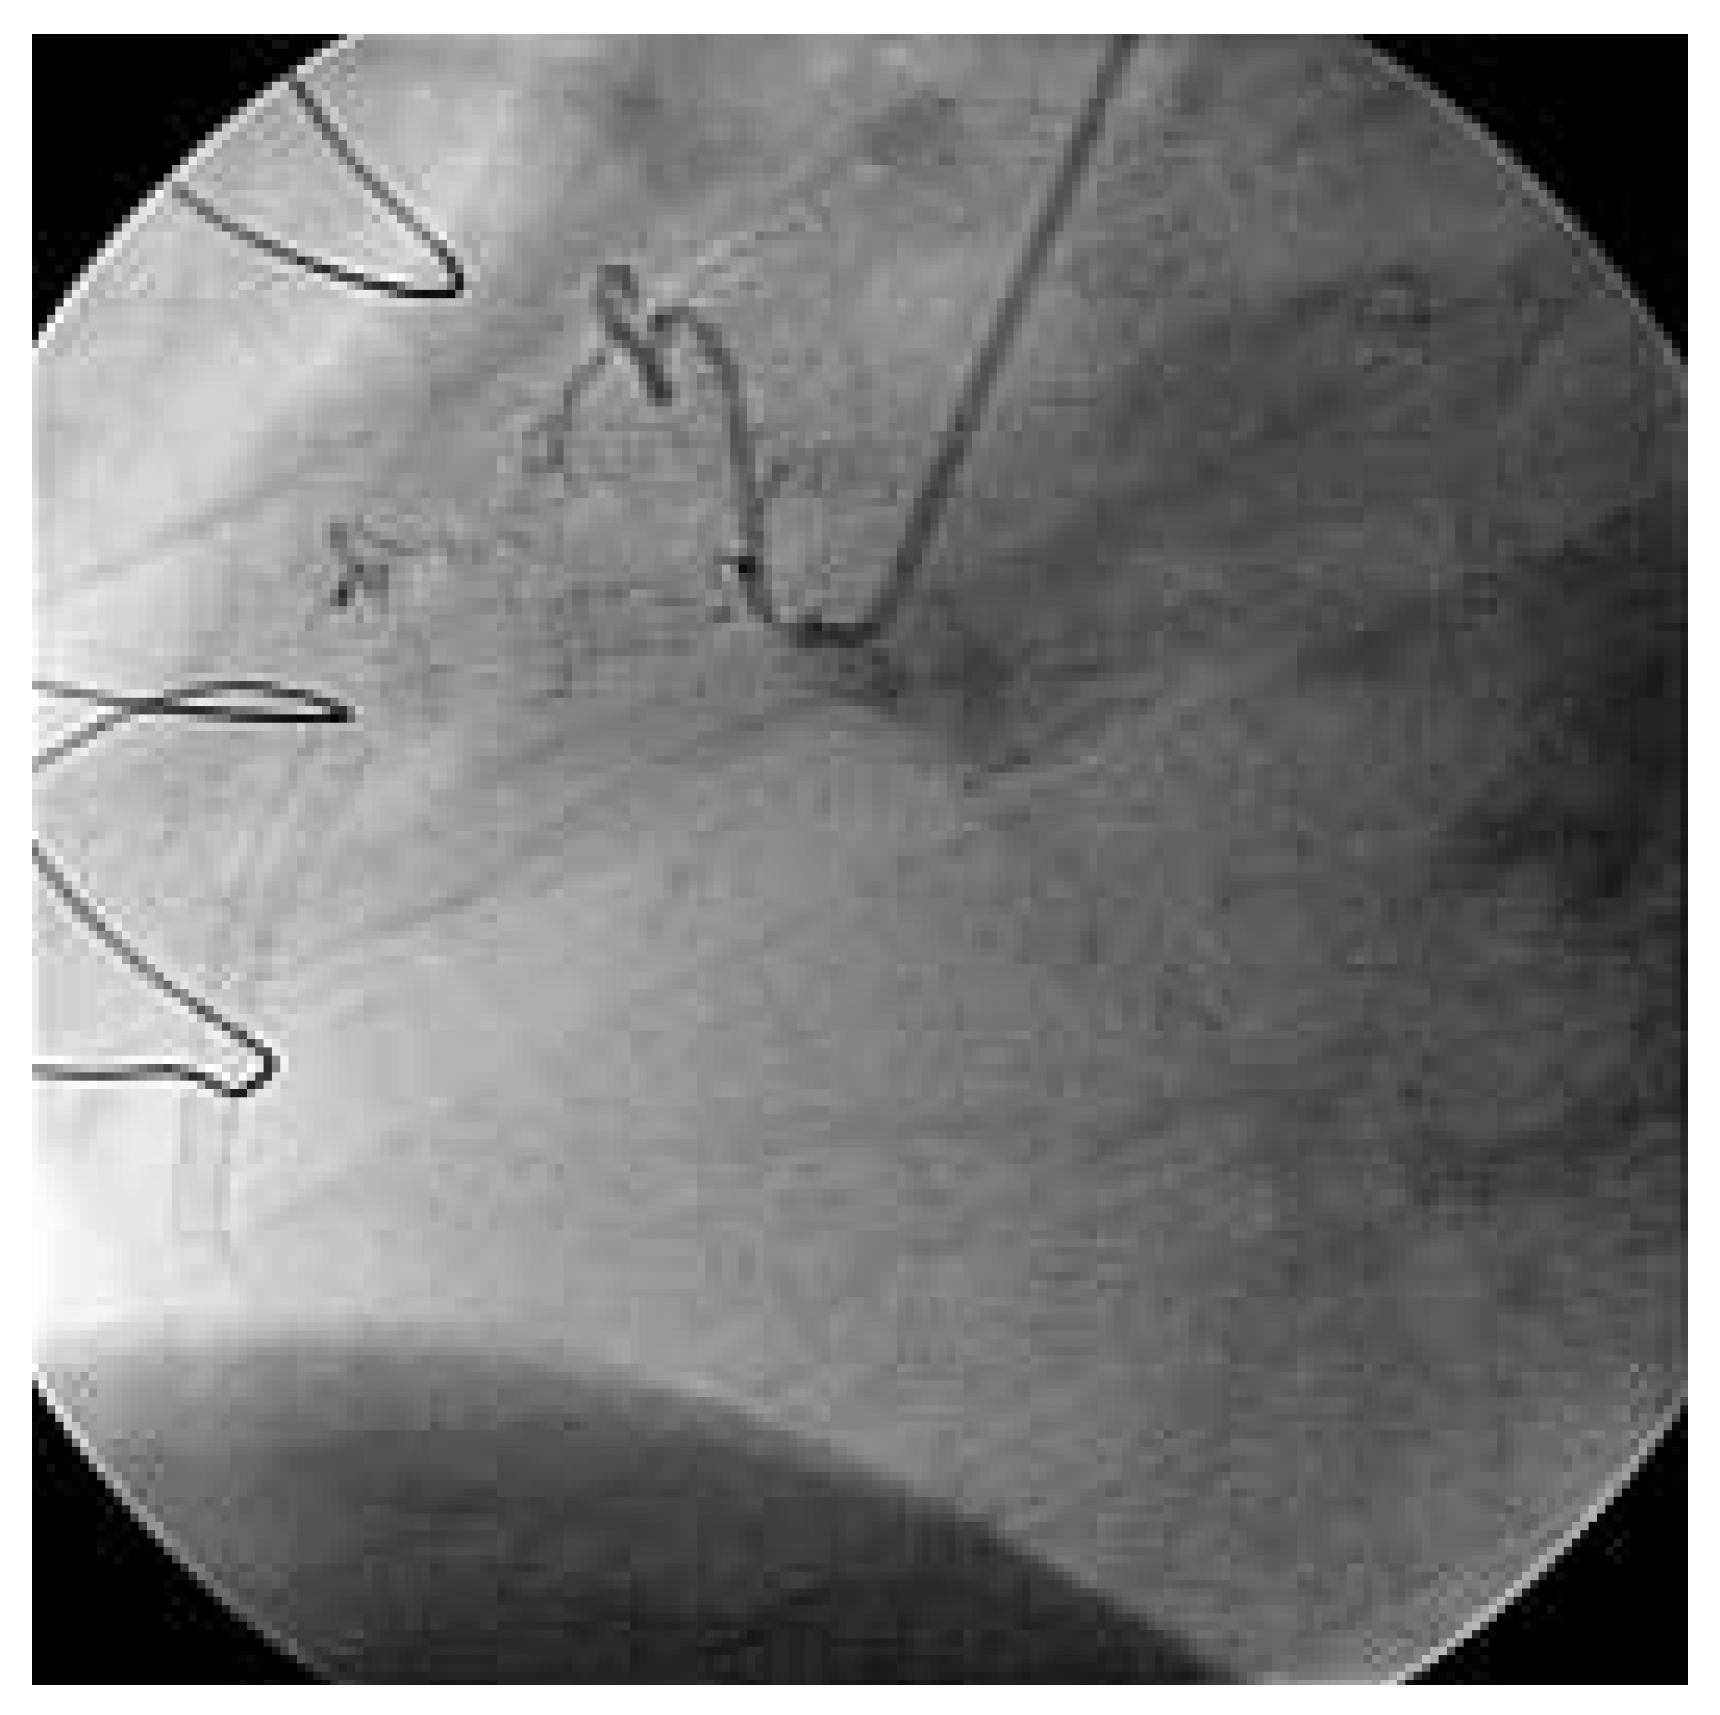

Abbildung 4. Nach mehreren Durchgängen mit dem «Export™»-Thrombus-Aspirationskatheter, bei denen thrombotische Debris aspiriert wurde, kommt der RCA zur Darstellung, der Fluss ist wieder hergestellt. Das angiographische Resultat ist sehr zufriedenstellend.

Der 74jährige Patient wurde 1991 chirurgisch revaskularisiert (LIMA zu Diagonal-Ast und RIVA, Venengraft zum Ramus intermedius und Posterolateral-Ast [PLA]. 1999 wurde eine perkutane Intervention am RCAmit Stent-Einlage vorgenommen. Zwei Jahre später wurde der Venengraft mit einem Stent versorgt und der RCA rekanalisiert, erneut dilatiert und eine Brachytherapie appliziert. Im Herbst 2003 begann der Patient erneut über typische und reproduzierbare Präkordialgien, entsprechend einer CCS-Klasse III, zu berichten. Eine Rekoronarangiographie zeigte weiterhin einwandfreie Verhältnisse des LIMA- und des gestenteten Venengraftes, die RCA war jedoch am Abgang langstreckig verschlossen (Abb. 2). Der Herzchirurg war der Meinung, dass eine erneute perkutane einer chirurgischen Revaskularisation vorerst vorzuziehen wäre. Eine intravenöse Abciximab-Gabe wurde begonnen. Nach schrittweiser Drahtpassage, alternierend mit repetitiver Ballondilatation bis über die Bifurkation, intrakoronarer Nitrat-Gabe und Einlage zweier langer beschichteter Stents bis über dem mittleren Gefässdrittel, stand die Kontrastmittelsäule immer noch im proximalen Gefässanteil still (Abb. 3). Wir entschieden uns zur Verwendung des «Export»-Thrombus-Aspirationskatheters. Erst nach mehreren Durchgängen mit dem Aspirationskatheter, bei denen thrombotische Debris aspiriert wurden, kam das grosse Gefäss zur Darstellung und wurde der Fluss wieder hergestellt. Das angiographische Resultat war nach Vervollständigung der Intervention sehr zufriedenstellend (Abb. 4). Der Patient war nach der Intervention während 8 Monaten beschwerdefrei und leistungsfähig. Aufgrund eines Prostatakarzinoms wurden mehrere urologische Eingriffe und eine lokale Bestrahlungstherapie notwendig, weshalb Clopidogrel und die orale Antikoagulation sistiert werden mussten. Die perioperative Periode verlief ohne kardiale Komplikationen, der Patient jedoch wurde wieder symptomatisch (CCS-Klasse II). Nicht zuletzt, weil nun wahrscheinlich eine chirurgische Revaskularisation nicht mehr zu umgehen ist, kann sich der Patient zurzeit noch nicht zur diagnostischen Koronarangiographie entschliessen.